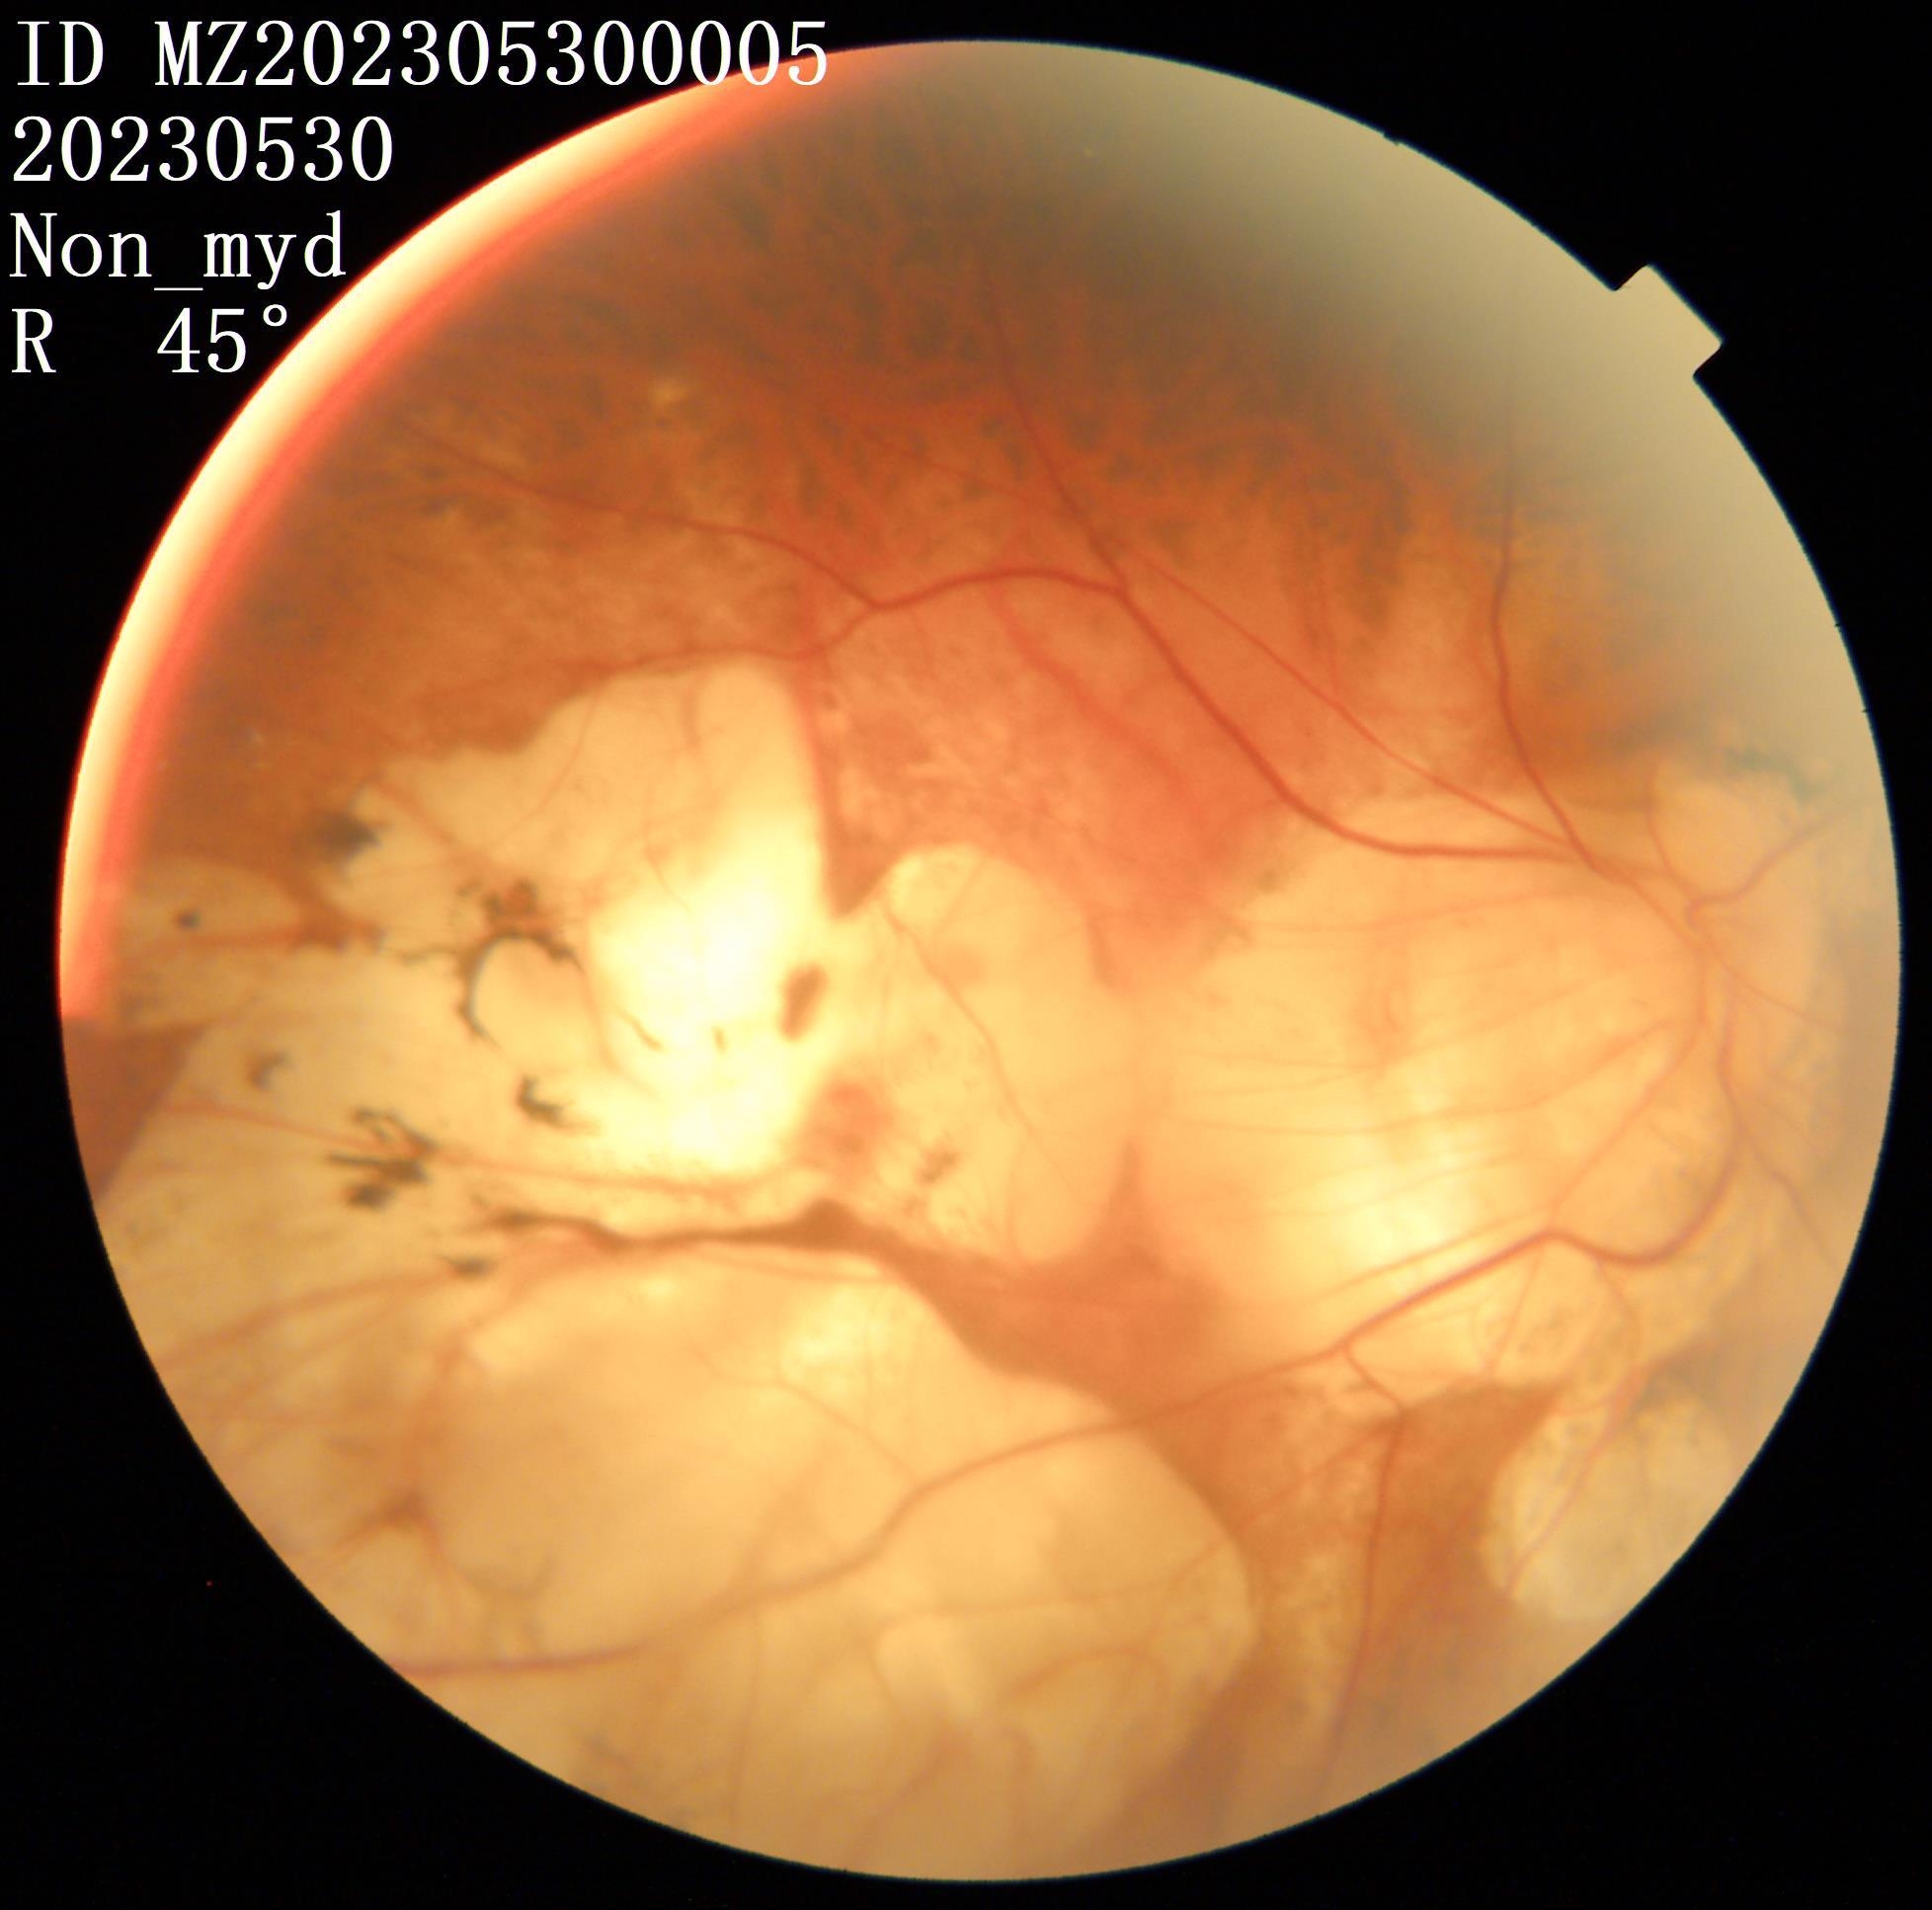

我检查以后发现他双眼的裸眼视力都非常差,右眼只有50公分数指,左眼只有0.02,矫正视力右眼戴2000度眼镜勉勉强强可以看0.05,左眼戴1900度眼镜也只能勉勉强强看到0.15,双眼晶状体轻度浑浊,玻璃体浑浊。最令我吃惊的是老人家双眼黄斑区视网膜不仅萎缩得像一张薄纸,而且还有劈裂性脱离及视网膜下陈旧性疤痕形成。

右眼手术以前眼底(萎缩、劈裂性脱离及视网膜下陈旧性疤痕)

右眼手术以前照片